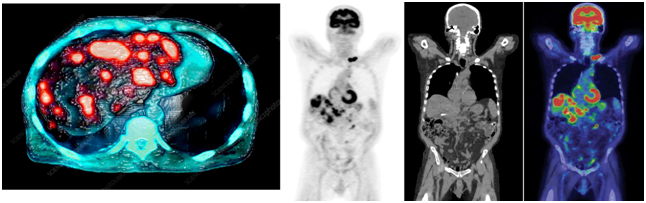

Позитронно-эмиссионная томография

Особенность исследования позитронно-эмиссионной томографии (совмещённая с компьютерной томографией) в том, что в этом случае используются радиофармпрепараты, например, радиоактивная глюкоза, которая вводится в организм перед исследованием.

Помимо размера опухоли, с помощью ПЭТ-КТ специалисты могут оценить метаболическую активность (т.е. степень накопления радиофармпрепарата в опухоли) как первичных, так и вторичных образований.